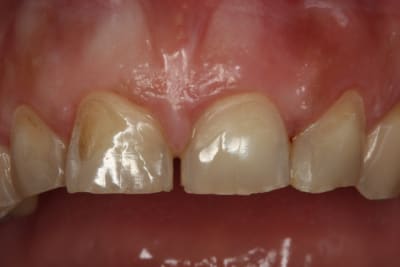

Bonjour,ma patiente présente des érosions des faces vestibulaires et est gênée esthétiquement car elles se colorent en quelques semaines après un détartrage et polissage. Elle me dit qu'elle serre les dents la nuit mais ne bruxe pas ( du moins son mari n'entend rien...). Au niveau alimentaire, il n'y a pas une consommation excessive de fruit, crudité, ni de boisson sucrée gazeuse. Ces érosions sont elles du au fait que la patiente serre les dents? Peut on envisager de les reconstituer avec des facettes ou est ce plutôt contre indiqué dans son cas? Merci pour vos conseils.

je suis quand même étonné qu'elle ne bruxe pas compte tenu des usures des bords libres antérieurs et des encoches en particulier 13 et facette abrasion versant V de 34.

en faisant bien attention à l'occlusion et aux trajets des contacts par rapport aux bords de collage des facettes, je pense qu'il n'y a pas de contre indication à la facette. prévoir peut être une gouttière de protection nocturne.

Le bandeau d'émail restant périphérique est caractéristique d'une érosion chimique...

Pas toujours, l'émail saute où s’exercent les contraintes, si c'est au milieu de la face vestibulaire (pour des incisives) il en restera en dessous.

Dans ton cas, sur les photos il semble y avoir un recouvrement incisif excessif, d'où surpression en propulsion, il faudrait aussi voir si elles ne sont pas (11 et 21, en fait le bloc incisivo-canin) trop lingualées, cela pourrait expliquer les deux fêlures verticales de l'émail.

La facette d'usure sur la 43 très marquée par rapport aux collatérales postr... le bloc antr mandibulaire appuie fort (c'est un contraint?).

Si tu fais des facettes tu risques d'avoir les même fêlures en vestibulaire ou pire, il faudrait tester ou "libérer" la mandibule, si quelqu'un a une idée?